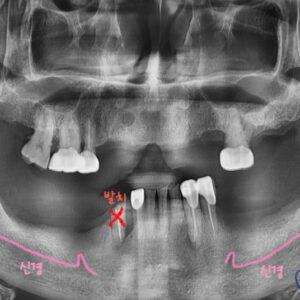

정확히 보기 위해 파노라마 엑스레이 사진을 찍었는데요.

빨간색 화살표 부분을 보시면

유치가 깨져서 일부가 남아있고,

후속 영구치가 없는 것을 확인 할 수가 있습니다.

유치의 뿌리도 다 녹아서 거의 남아있지 않으므로,

임플란트를 심을 위치를 확인하고 신경까지의 거리를 보기 위해

엑스레이를 찍어 확인합니다.